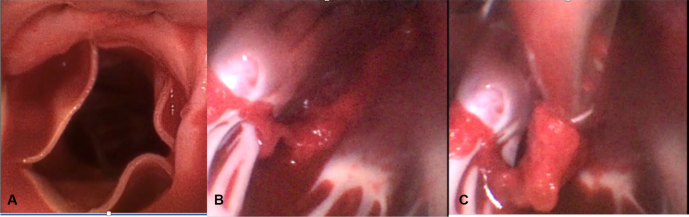

After a horizontal aortotomy a large single-use flexible bronchoscope (4 Broncho Regular 5.0/2.2; Ambu aScope) was passed beyond the prosthetic aortic valve into the apex of the left ventricle. Using a combination of long, straight grasping instruments, and a toothed biopsy forceps placed through the working canal of the scope, the entire thrombus was removed under vision (Figure 2). Crossclamp time was 79 minutes. Video 1 illustrates ease of retrieval.

Figure 2.

Flexible bronchoscope provides excellent visualization on entry through the aortic valve (A), of clot adherent to the trabecula in the left ventricle (B), allowing for easy retrieval with a minimally invasive forceps grasper (C).